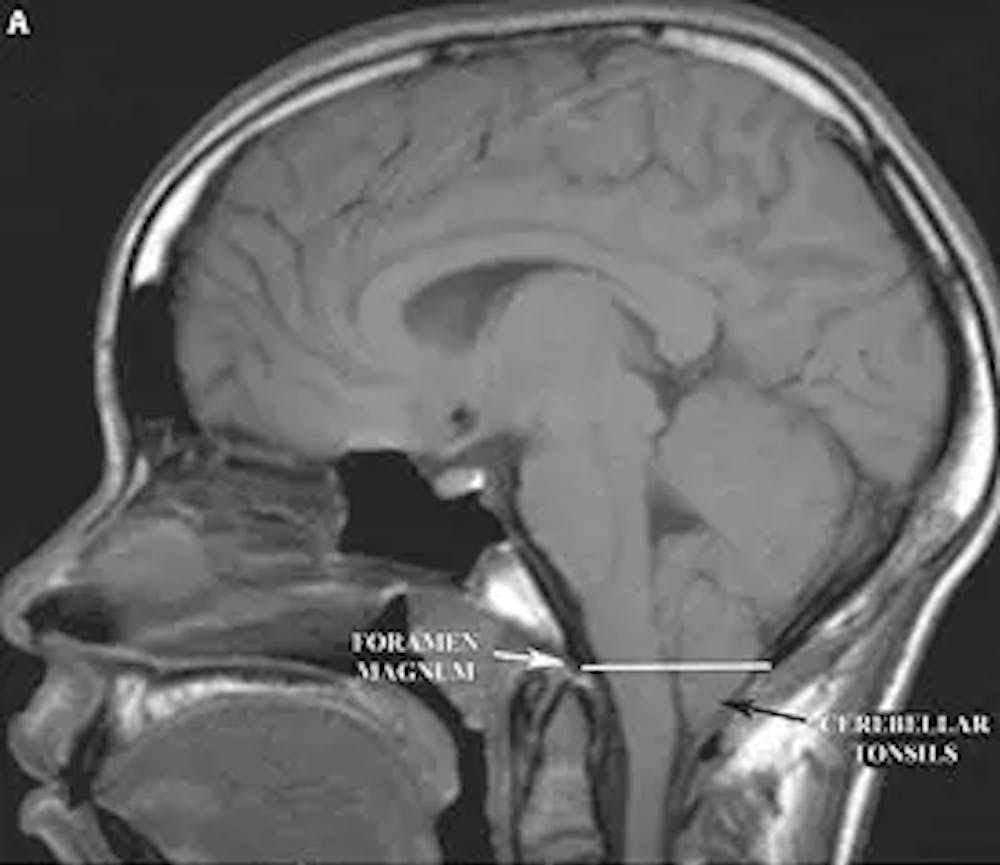

A) Resonancia magnética ponderada T1 sagital del cerebro que demuestra la protrusión de las amígdalas cerebelosas por debajo del foramen magnum (indicado por la línea blanca). Esta es una malformación de Chiari tipo I.